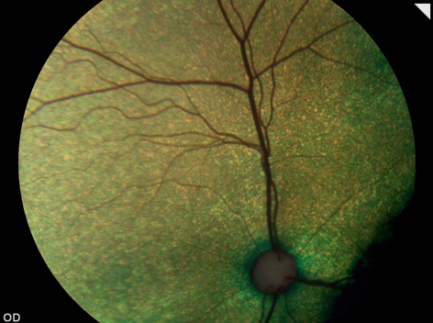

Una retinografía es un procedimiento diagnóstico que nos permite, a modo de fotografía, obtener imágenes en color de la retina. Es una prueba que proporciona una información muy valiosa sobre el estado de la retina y el nervio óptico.

Para realizar una retinografía en ocasiones es necesario dilatar la pupila mediante la instilación de colirio para poder observar con mayor extensión la retina. Una vez que la pupila ya está dilatada se procede a tomar una serie de imágenes con el Retinógrafo Ocular. Se trata de un procedimiento no invasivo que no ocasiona molestias por lo que en general se realiza sin necesidad de sedar al paciente.

La retinografía es una herramienta fundamental en la detección precoz y el seguimiento de determinadas patologías relacionadas con el nervio óptico (hipoplasia, coloboma, neuritis, …), la retina (degeneraciones, desprendimiento retina, procesos inflamatorios, hemorragias …) y para detectar alteraciones vítreas tales como hemorragias y degeneraciones.